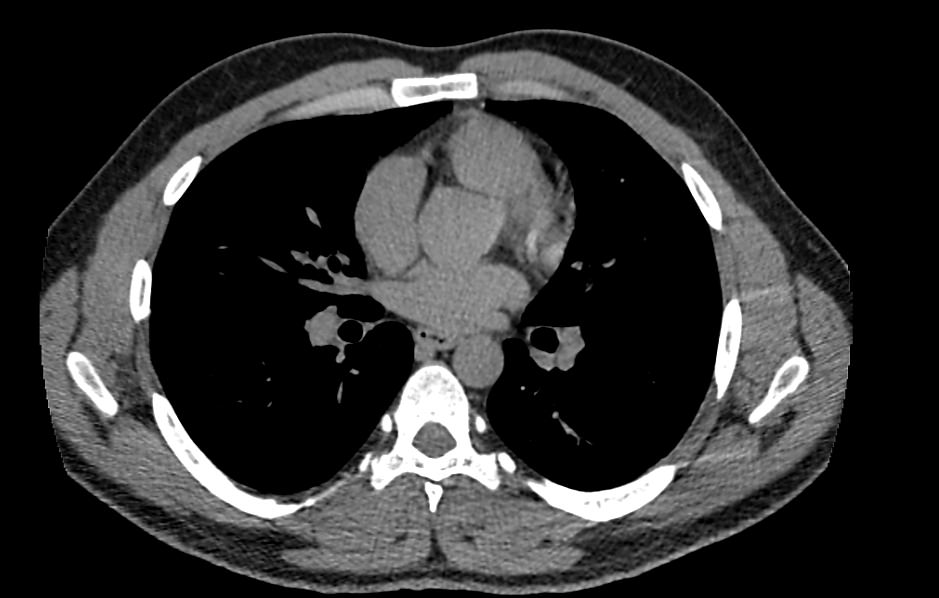

Одним из наиболее информативных методов исследования органов средостения является компьютерная томография. В основе метода лежит использование проникающего действия ионизирующего излучения для получения подробных снимков строения внутренних органов.

Инновационные технологии, которыми оснащены компьютерные томографы, послойно сканируют анатомическую область с шагом от 0,5 мм. В результате получаются снимки тонких срезов исследуемой зоны в мельчайших подробностях. С помощью цифровых приложений на основании полученных данных можно реконструировать трехмерные модели внутренних органов, что позволяет оценить структуру зоны исследования и близлежащих тканей.

Что показывает КТ органов средостения?

- наличие онкологии и метастазов;

- туберкулез и другие инфекции;

- патологии диафрагмы и бронхов;

- последствия травм;

- состояние лимфоузлов;

- индивидуальные анатомические особенности;

- патологии вилочковой железы;

- новообразования из нервной ткани;

- опухоли в жировой соединительной ткани;

- патологии мышечной ткани и сосудов;

- кисты;

- эмфизему средостения;

- абсцесс, эмпиему средостения;

- аневризму аорты

- воспалительные процессы;

- болезни сосудов и тромбоэмболию.